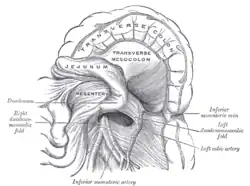

En anatomía, el yeyuno es una de las partes del intestino delgado de los mamíferos; se encuentra entre el duodeno y el íleon.[2][3] Su función es realizar la absorción de las sustancias del quimo alimenticio.[3] En este tramo del intestino delgado actúa el jugo intestinal, que degrada al mínimo los hidratos de carbono, las proteínas y los lípidos. La pared del yeyuno presenta las vellosidades intestinales, cuya función es traspasar al torrente sanguíneo las sustancias anteriormente señaladas. En síntesis, presenta vellosidades que absorben los nutrientes hacia la vena intestinal para ir a parar a la sangre.

Fosa yeyunoduodenal. -